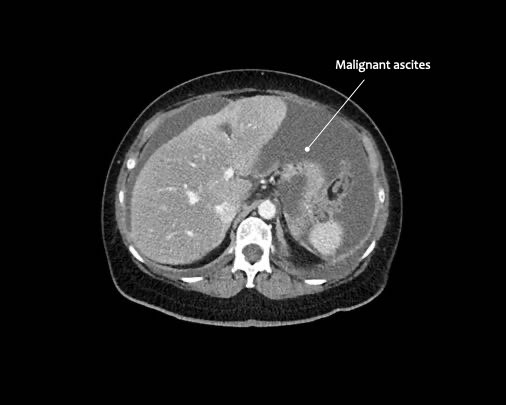

Cổ trướng

Sự hiện diện của cổ trướng là một dấu hiệu đáng lo ngại, do các nốt phúc mạc sản sinh ra dịch này và do đó có thể là gợi ý đầu tiên cho thấy ung thư phúc mạc (PC) đang hiện diện.